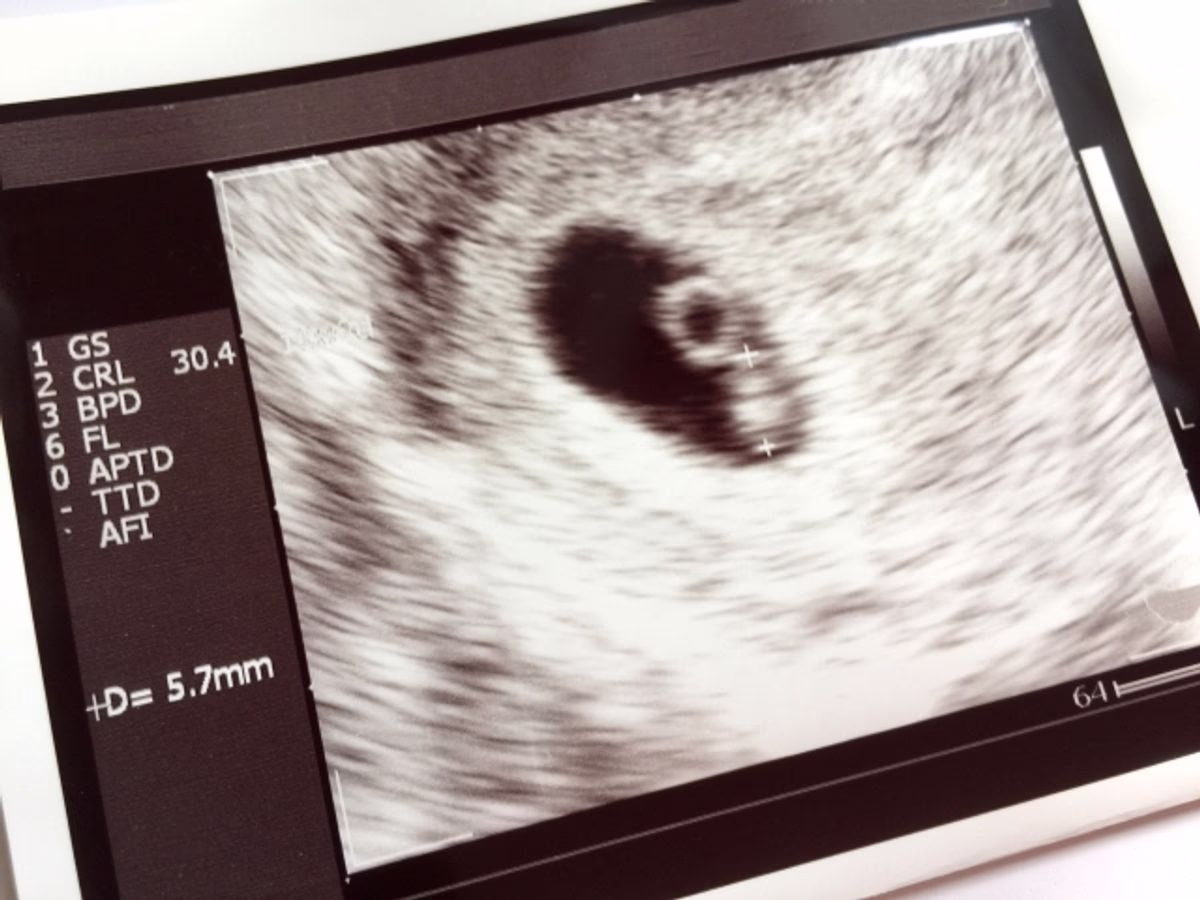

エコー検査(超音波検査)とは、人間の耳では聞くことのできない高い周波数の超音波を発生させる機械(プローブ)をカラダの表面に当て、カラダの臓器から跳ね返ってきた超音波を画像として表示する検査のことをいいます。

産婦人科で行うエコー検査は、膣の中にプローブを挿入する経膣エコーとお腹の上からプローブを当てる経腹エコーがあります。

妊婦健診で行うエコーの目的は、胎児の大きさなど発育状態を確認したり、異常の早期発見をすることです。

- 妊娠週数に応じた大きさかCRL(頭からお尻の長さ)をチェック

- 妊娠週数に応じた大きさかCRL、BPD(あたまの横幅)をチェック